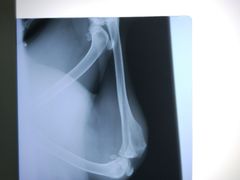

• 骐奇宠物诊疗中心(南亭公路店)

• -骐奇宠物诊疗中心(南亭公路店)

A*果果美妆铺* | 18-05-17

报错